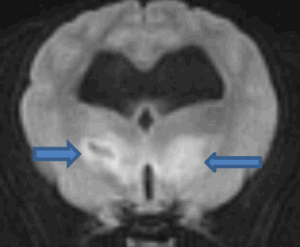

- Неврологическими синдромами, которые связаны с проявлением синдрома внутричерепной гипертензии, появляющимся в результате блока ликворных путей зубом второго позвонка. Это проявляется в виде множества различных неврологических симптомов. Собака не может стоять на лапах, падает на бок, хаотично бьет лапами, закручивает голову резко в сторону и вслед за головой переворачивается на 360 градусов и может продолжать кувыркаться так, пока ее не остановили. Мелкие породы собак склонны к развитию гидроцефалии, часто протекающей бессимптомно, и если у собаки имеется гидроцефалия, она может резко усугубиться за счет блока ликворных путей и повышения давления в желудочках головного мозга. Резкое повышение давления в головном мозге приводит к развитию синдрома внутричерепной гипертензии.

Также могут быть замечены симптомы поражения мозга, что может быть следствием нарушения циркуляции ликвора и развитием или прогрессированием гидроцефалии, которая часто у 95 % карликовых пород собак(Braun,1996) присутствует, но без клинических признаков. У животного гидроцефалия может также сопровождаться сиринго(гидро)миелией.

Компрессия базилярной артерии зубовидным отростком эпистрофея может вызвать появление таких симптомов, как дезориентация, изменение поведения, вестибулярный дефицит.